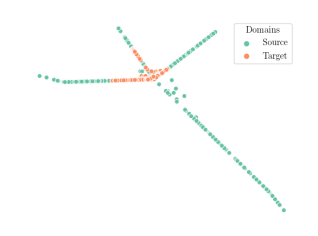

We compare the -distance of categorical features and domain features. Fig. 5 (a) shows that domain difference is higher in domain features than in categorical features. This indicates that domain features contain more domain information whereas categorical features are more domain-invariant. Fig. 6 shows the t-SNE plot of categorical features in both domains for MIDNet. From Fig. 6 (a), we observe that the categorical features learned by MIDNet enable the anatomical classification. Fig. 6 (b) shows that the learned categorical features are domain-invariant.

In addition, we utilize t-SNE plots for feature visualization in Fig. 10. Comparing Fig. 10 (a) and Fig. 10 (b), we observe that with mutual information disentanglement, (1) samples from the same category are more tightly clustered (see the top row) and (2) the source domain and the target domain are overlap more (see the bottom row). This indicates that mutual information disentanglement is important for learning categorical-focused and domain-invariant features. Fig. 10 (a), (c)-(d) show that the proposed method outperforms other state-of-the-art methods for learning category-discriminative and domain-invariant features, especially for unseen categories in the target domain (e.g., (a) vs. (d)).